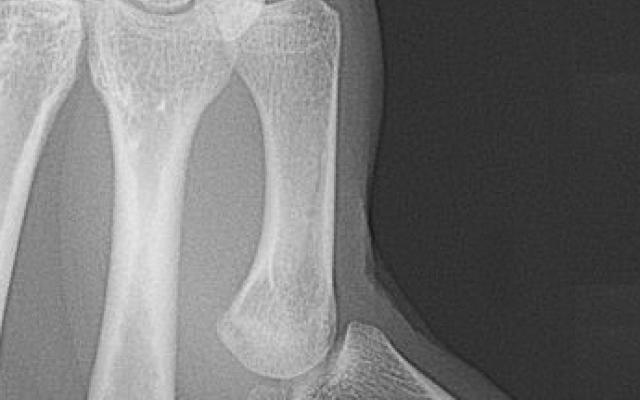

Een 22-jarige man meldde zich op de Spoedeisende Hulp met een pijnlijke linker duim na een val op uitgestrekte handen. Bij lichamelijk onderzoek was de stand van de linker duim afwijkend; er was sprake van een hyperextensiestand van 80° in het metacarpofalangeaal(MCP)-gewricht (figuur a). De patiënt kon de duim in het MCP-gewricht niet flecteren. Daarnaast stond de duimmuis in adductie en kon de patiënt deze niet abduceren. Een röntgenfoto liet een subluxatie zien van het MCP-gewricht zonder aanwijzingen voor een fractuur (figuur b). De duim kon vrij eenvoudig manueel gereponeerd worden; een röntgenfoto in gips ter controle liet een…